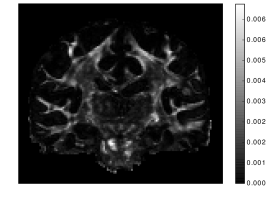

Figure 8 (left) highlights the regions of the brain in which NODDI-SH features a lower MSE than NODDI. Almost all the white matter appears to be white, which seems to indicate that NODDI-SH is able to reconstruct the diffusion signal more accurately. These results could be explained by the fact that the Watson distribution is not able to model most of the brain fiber configurations, while NODDI-SH can model any kind of fiber arrangement including fanning and crossing. In most of the gray matter and CSF NODDI fits the diffusion signal slightly better than NODDI-SH, although the absolute value of the difference of the MSE is lower than that obtained in white matter (Figure 8, right).

| NODDI MSE NODDI-SH MSE | NODDI MSE - NODDI-SH MSE |

|---|---|

![]() |